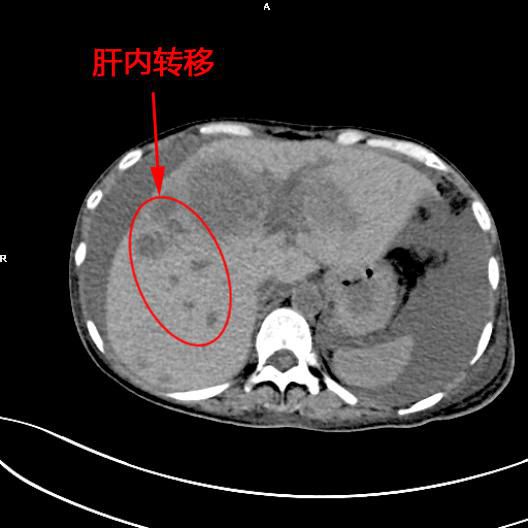

患者陳女士,57歲,汕頭潮南人,2個月前出現右上腹痛,在汕頭大型三甲醫院确診爲膽囊癌,因腫瘤爲晚期,已擴散至肝髒、十二指腸,患者放棄在汕頭治療,回家後自行采用中藥治療。近期右上腹痛加重,反複排黑便,遂來我院住院,診斷爲膽囊癌伴活動性出血。

李旭丹主任在DSA引導下找到腫瘤的供血動脈——膽囊動脈,通過股動脈穿刺置入微導管将栓塞材料送達并釋放于腫瘤供血動脈,成功将動脈堵住,掐斷了腫瘤的供血。手術達到了預期目的,不但膽囊出血得到根除,也阻斷了腫瘤的營養供應,達到“餓”死腫瘤的目的,同時在腹腔幹灌注化療藥治療轉移病竈。